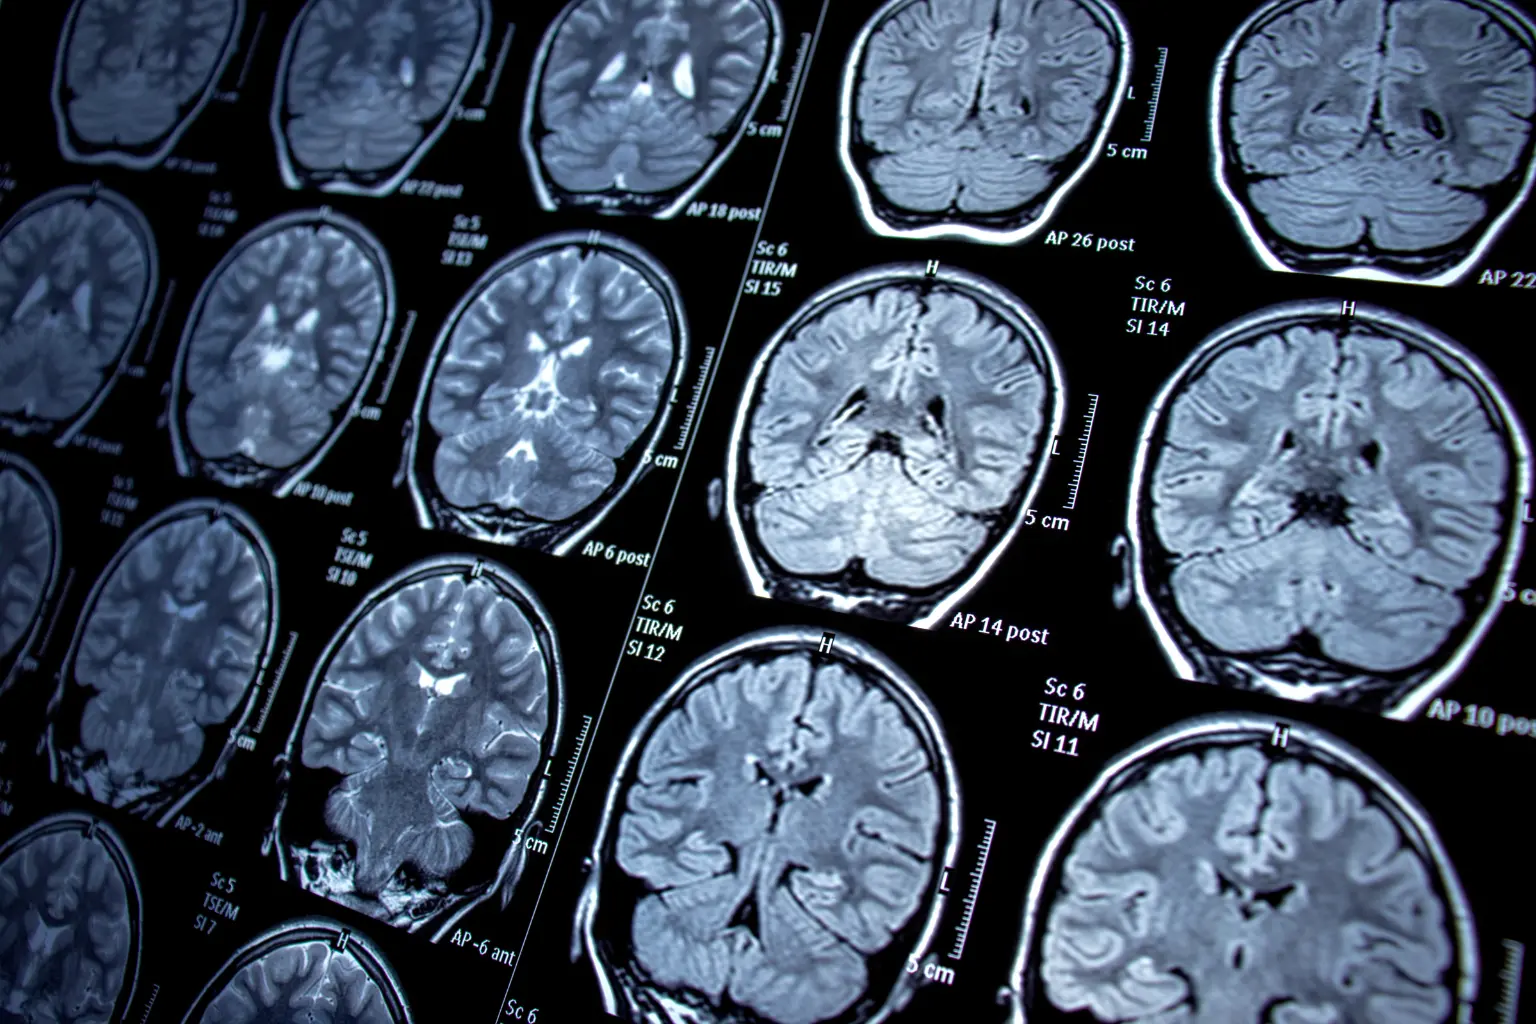

Nghiên cứu bằng EEG (điện não đồ) và fMRI cho thấy rằng não bộ có thể tăng hoạt động đột ngột trước khi ngừng hẳn. Sự “bùng sáng” này làm kích hoạt tạm thời các vùng: nhận thức, ký ức, cảm xúc, và nhận biết ngôn ngữ.